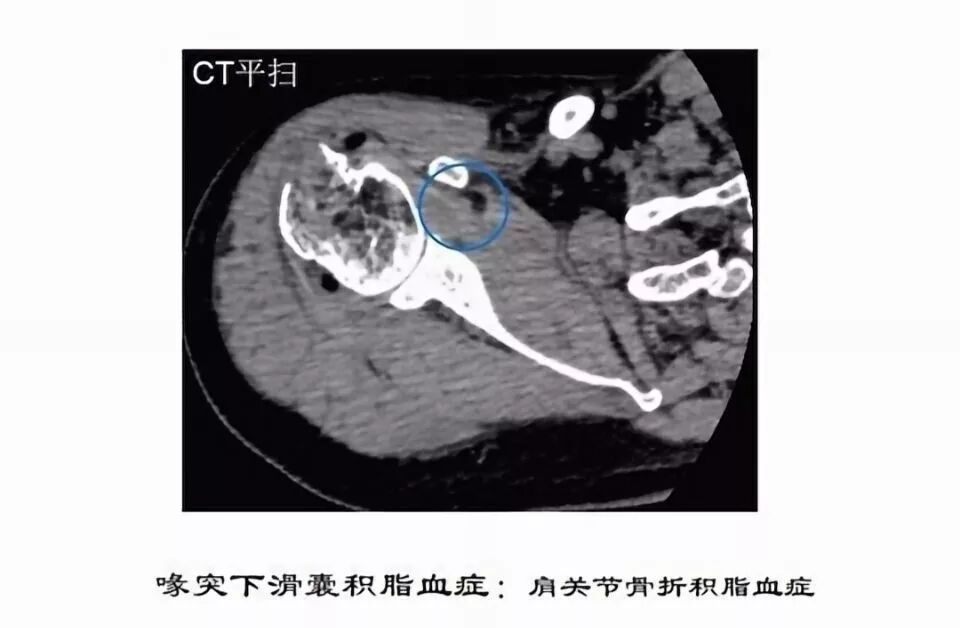

滑囊是关节囊外的囊性结构,可与关节囊相通,其作用是减少肌腱、骨和皮肤之间的摩擦。可以分为先天性滑囊和获得性滑囊。